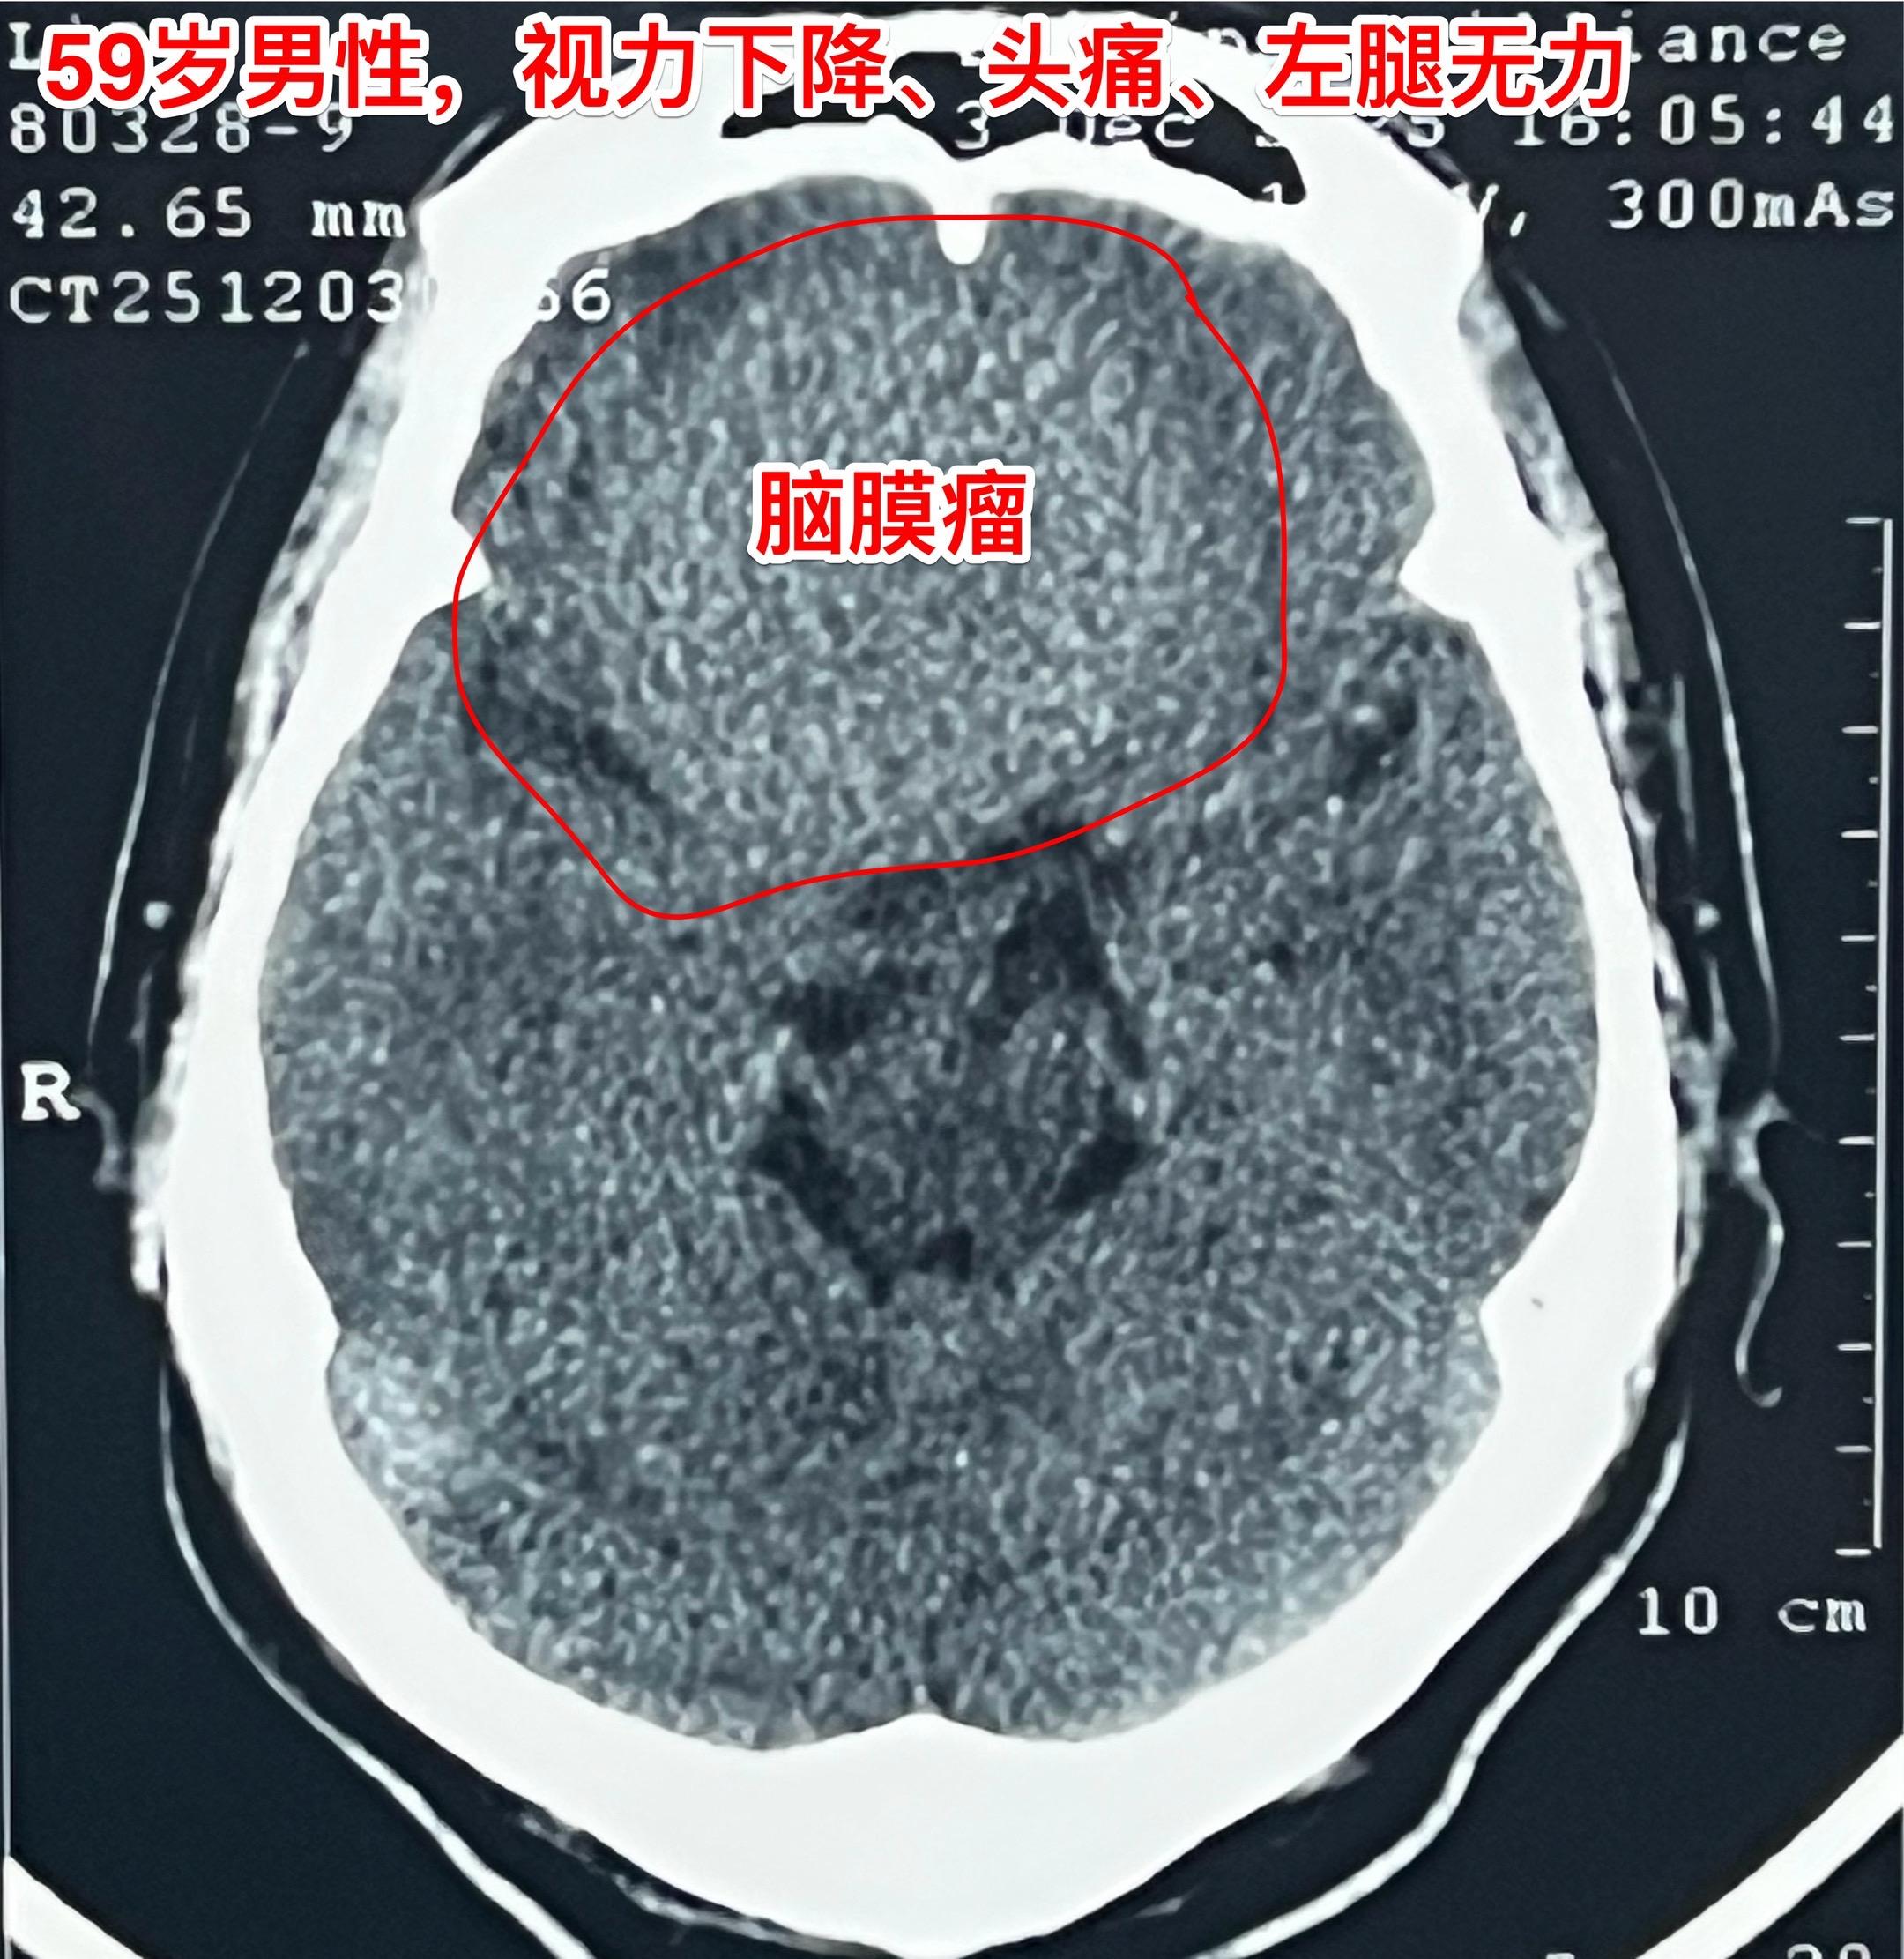

脑膜瘤长在不同的部位产生的症状也不同!这个59岁的内蒙古男性,最开始的...

脑膜瘤也会造成视力下降。66岁吉林省女性,退休后喜欢开车到处旅游,并在...